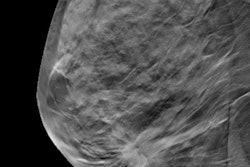

Images depict a 67-year-old woman who was recalled from screening for a small focal asymmetry in the left breast. (A) 2D mammographic image shows the lesion (arrow), which is difficult to see. (B) The digital breast tomosynthesis section image shows spiculated margins (circle). (C) The ultrasound image shows a corresponding irregular hypoechoic mass with angular margins. Pathologic evaluation revealed a 0.7-cm triple-negative invasive carcinoma. Image courtesy of RSNA.Finally, the researchers observed no significant difference in interval cancer rates between mammography (0.14 per 1,000) and DBT (0.2 per 1,000; p = 0.42).